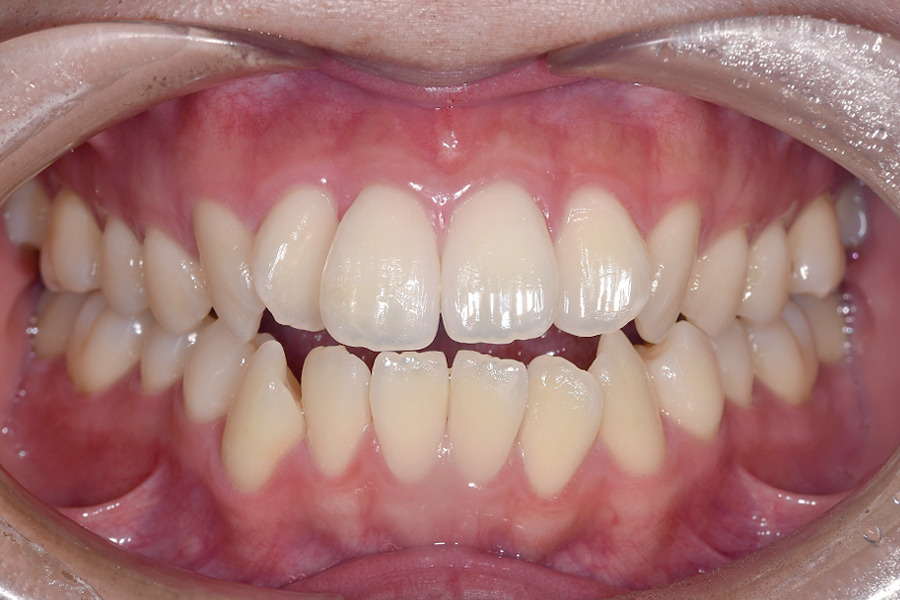

| 主訴 | 見た目を治したい、歯を白くしたい |

|---|---|

| 治療期間 | 1年6か月 |

| 治療費 | マウスピース矯正と ホームホワイトニングセット 1,022,350円(税込) |

| 治療内容 | 目立ちにくいマウスピース矯正 (非抜歯矯正) 歯と歯の間に隙間をつくることにより、歯列弓を広げながら治療を行いました。 また矯正用マウスピースをトレー代わりにし、ジェルを入れてホームホワイトニングを同時に行っております。 |

| 治療のリスク | ・後戻りする可能性があるのでリテーナーを最低でも矯正期間以上はつける必要があります。 ・ホワイトニング後、一時的に痛みが出る場合があります。 |